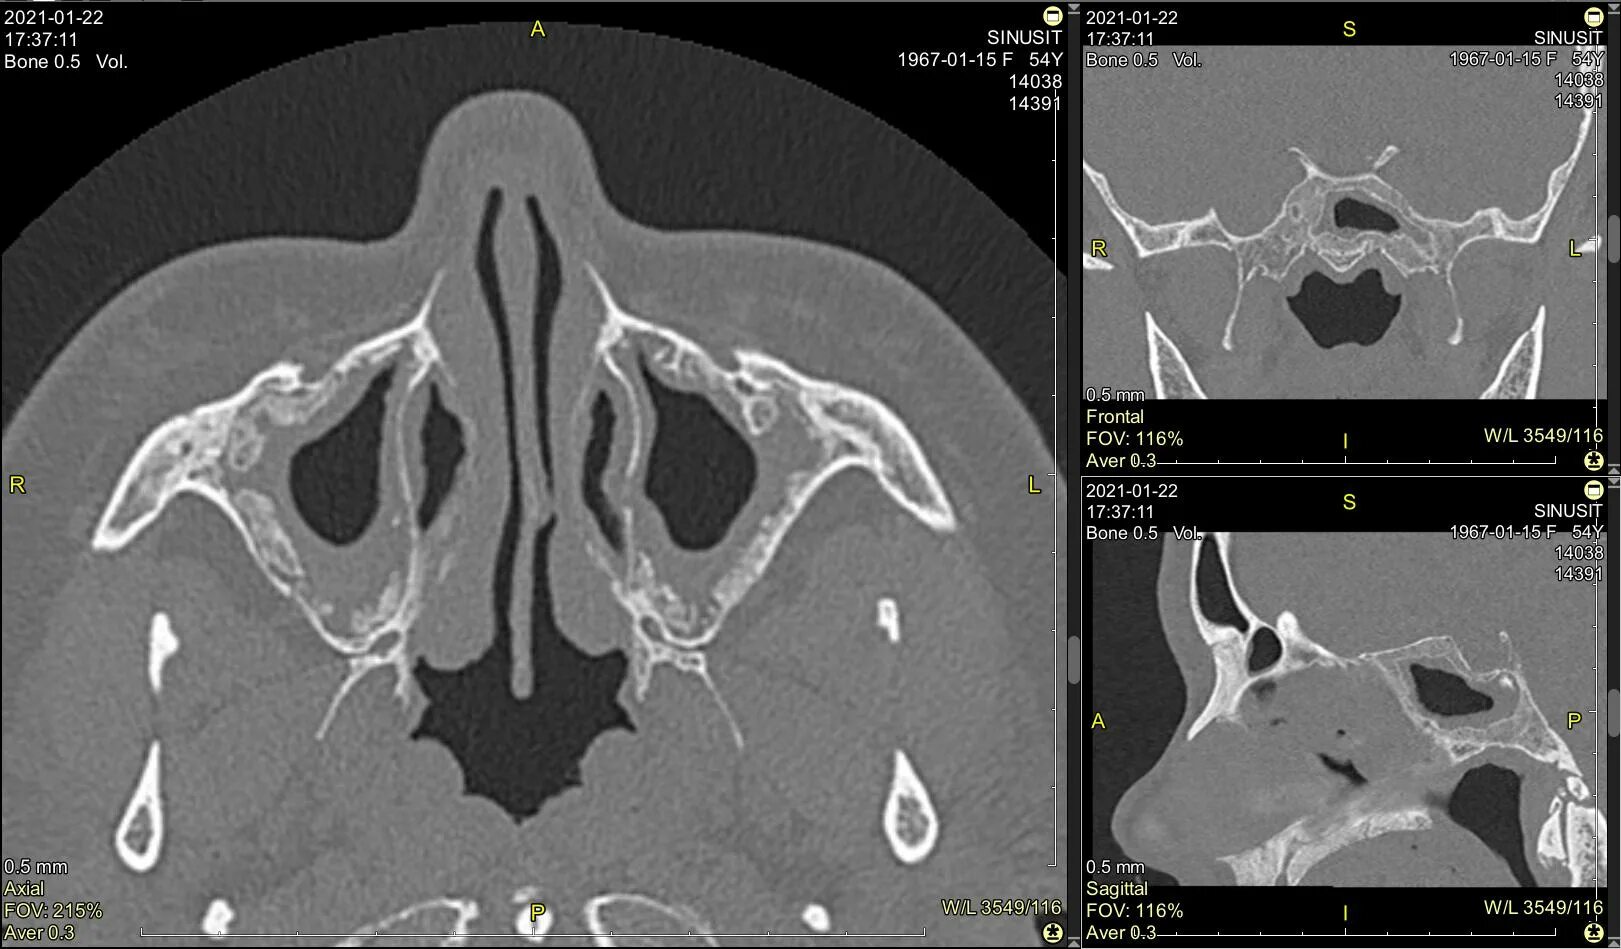

Синусит на кт